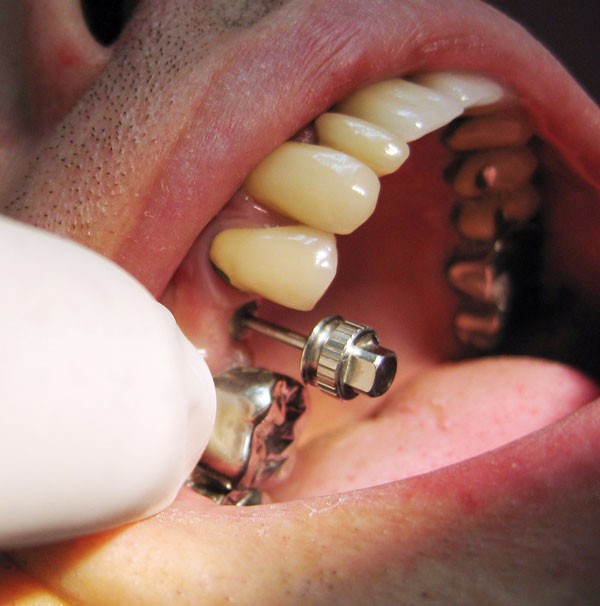

Dépose de la vis de cicatrisation (fig. 4) : l’assistante présente au praticien l’embout du tournevis adapté à la tête de vis de cicatrisation (fig. 5).

Puis le tournevis est calé sur l’embout (fig. 6) et la vis est retirée (fig. 7).

Mise en place du transfert (ici transfert de marque Zimmer) sur le tournevis (fig. 9 et 10) immédiatement après la dépose de la vis de cicatrisation afin d’éviter un retour de la gencive.